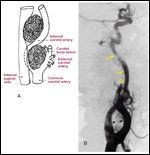

FIGURE 3

Vascular Involvement

Tumor location, displacement of major vessels, and patterns of involvement or invasion of surrounding structures aid in the diagnosis of paraganglioma. For example, carotid body tumors typically display the common carotid bifurcation with posterolateral displacement of the internal carotid artery (Figure 3A).[27] By contrast, vagal paragangliomas will displace both the internal and external carotid arteries anteriorly (Figure 3B), and are associated with erosion and widening of the jugular foramen.

Jugular paragangliomas may be distinguished from tympanic tumors based on early involvement of the skull base, erosion of the caroticojugular spine,[27,42] and destruction of the ossicular chain, which is unusual with tympanic tumors.[43]